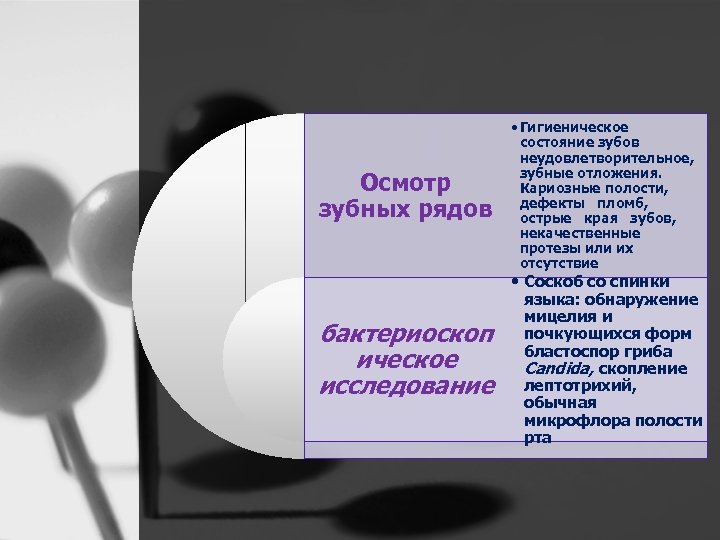

Осмотр зубных рядов • Гигиеническое состояние зубов чаще неудовлетворител ьное. Зубные отложения, кариозные полости. Дефекты пломб, острые края зубов

• Соскоб с очага поражения на спинке языка: обнаружение мицелия и почкующихся Дополнительные методы форм бластоспор исследования гриба Candida. Или бактериоскопическое обычная исследование микрофлора полости рта

Осмотр зубных рядов бактериоскоп ическое исследование • Гигиеническое состояние зубов неудовлетворительное, зубные отложения. Кариозные полости, дефекты пломб, острые края зубов, некачественные протезы или их отсутствие • Соскоб со спинки языка: обнаружение мицелия и почкующихся форм бластоспор гриба Candida, скопление лептотрихий, обычная микрофлора полости рта